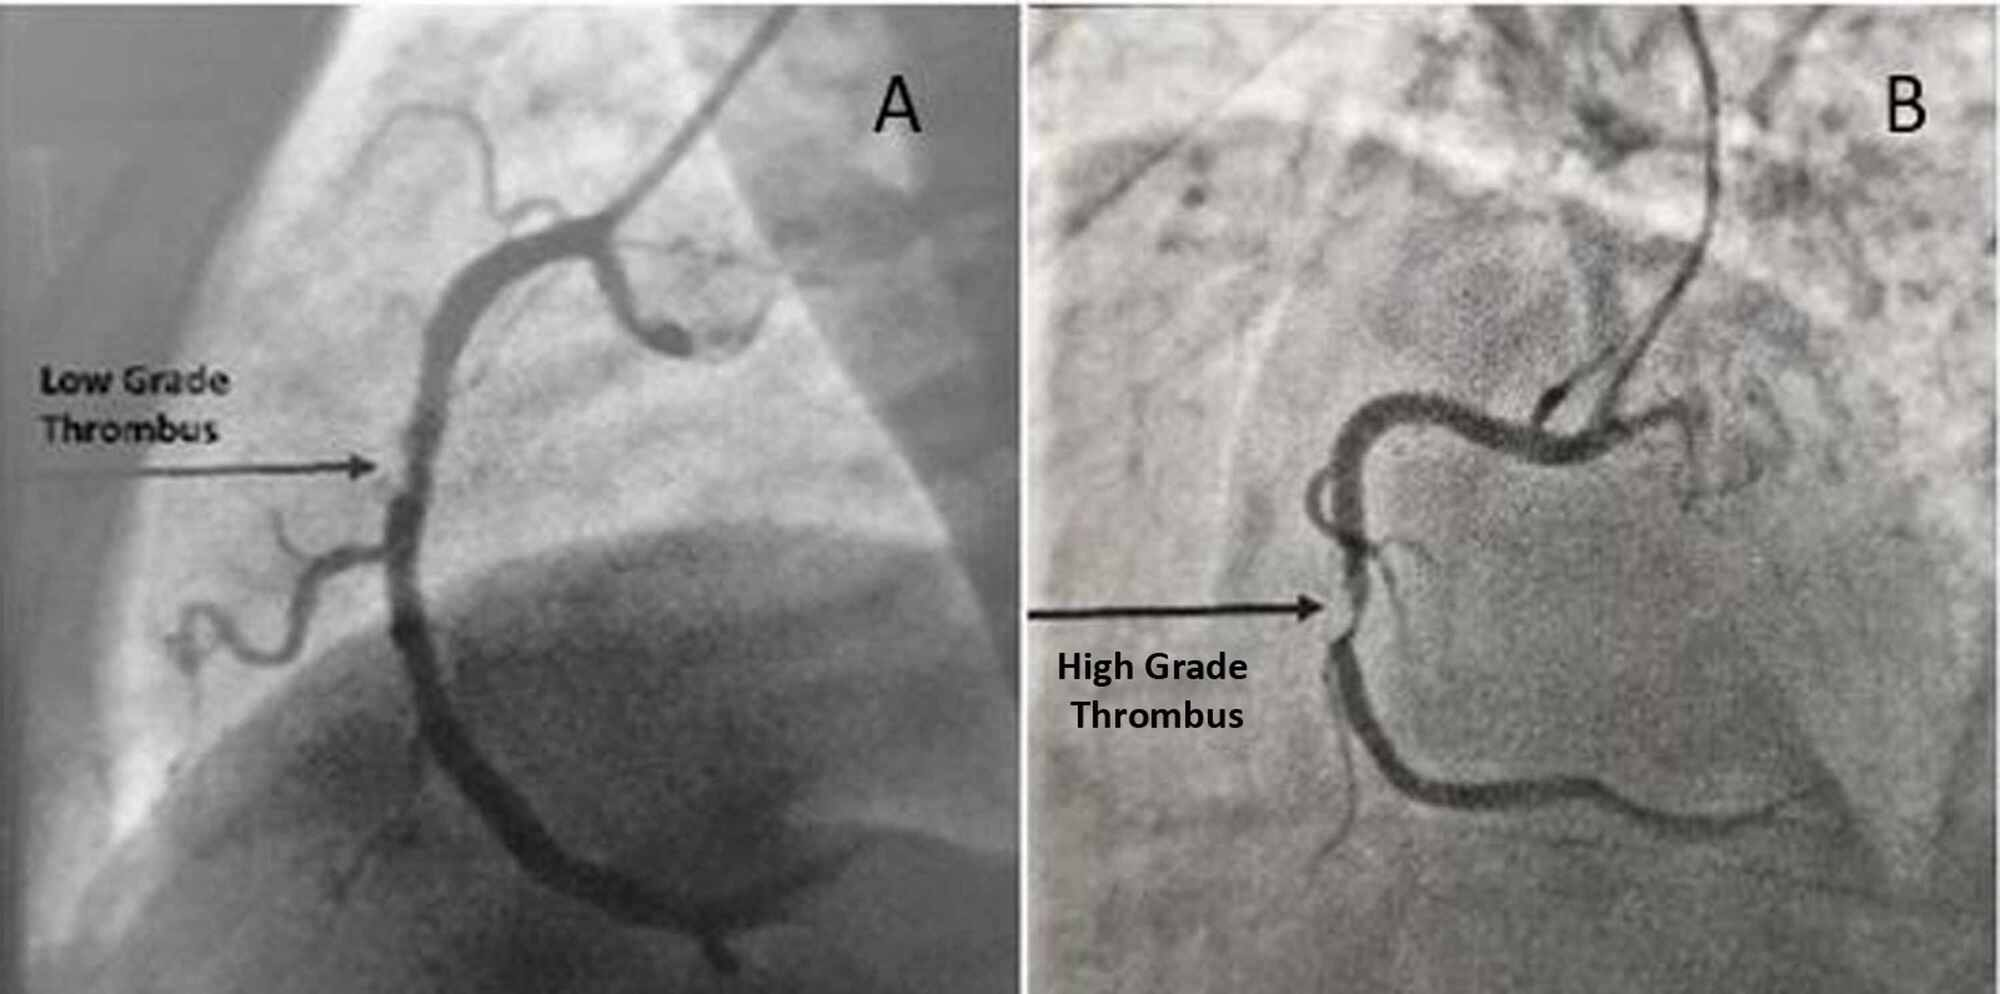

Patients who present with STEMI and a current or recent COVID-19 infection often have no culprit lesion, with a greater